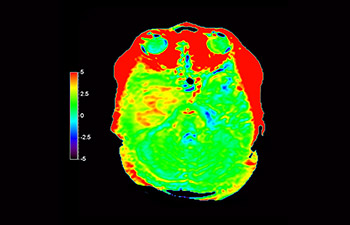

Glioblastoma

Brain with glioblastoma

with 3D APT